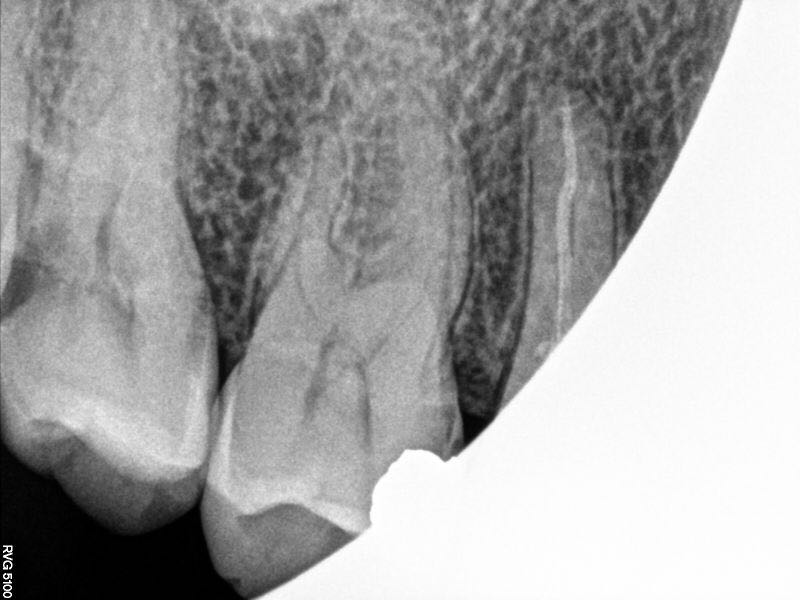

17牙冷++,叩-,松-,远中面探及龋坏及穿髓孔,x线片根尖未见明显暗影

行17牙根管治疗